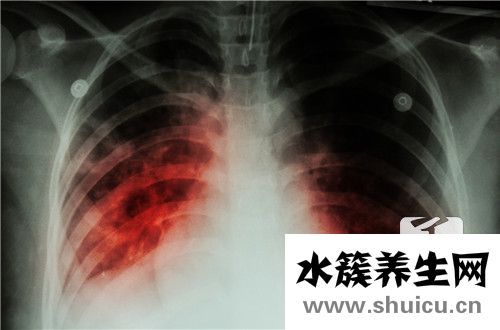

日常生活肺結(jié)核是常見病,會對患者的身心健康和日常生活產(chǎn)生很大影響。所以肺結(jié)核需要立即治療,肺結(jié)核治療需要一個漫長的全過程,所以在治療期間容易引起耐藥性。肺結(jié)核一旦引起耐藥,患者更擔心耐藥肺...